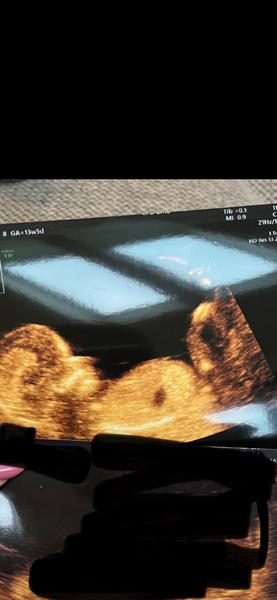

lze určit pohlaví?

bohužel nelze. Na snímku není vůbec zachycena patřičná oblast. 🙂